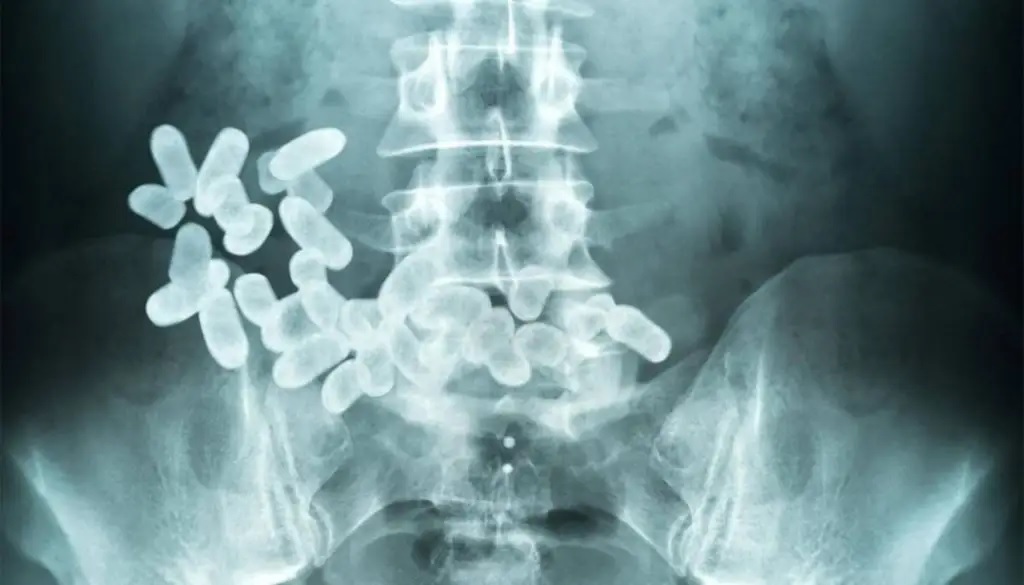

Dos bolivianas detenidas en un narcotour de contrabando expulsaron más de 80 cápsulas con cocaína

Al menos unas 80 cápsulas con cocaína habrían sido expulsadas el sábado por la noche por dos ciudadanas bolivianas, quienes viajaban en un tour de contrabando interceptado en Santiago del Estero, cuando se dirigía hacia Buenos Aires.

Sin margen de error, rápido expusieron que llevaban cápsulas en su organismo, obvio con cocaína. Urgente, los gendarmes condujeron a las bolivianas al Hospital Regional.

Y en horas de la madrugada iban expulsando al menos 80 cápsulas de cocaína. El final era incierto, desde lo cuantitativo, pero previsible penalmente para las dos pasajeras. El Liberal